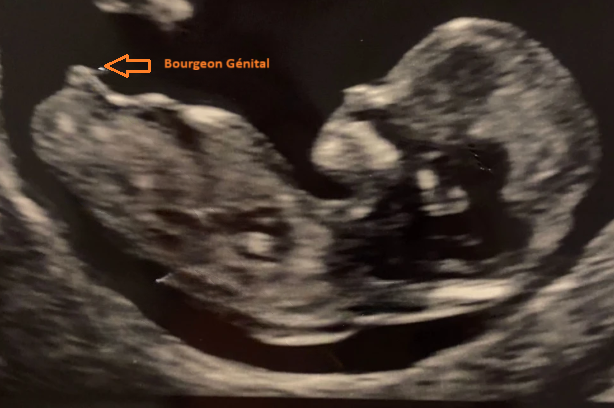

Pour une future fille 💖

Le bourgeon reste plus horizontal, presque parallèle à la colonne (angle < 30°). Il apparaît plus plat et moins proéminent.